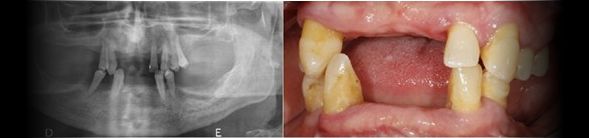

Caso clínico sobre Implantes Dentários